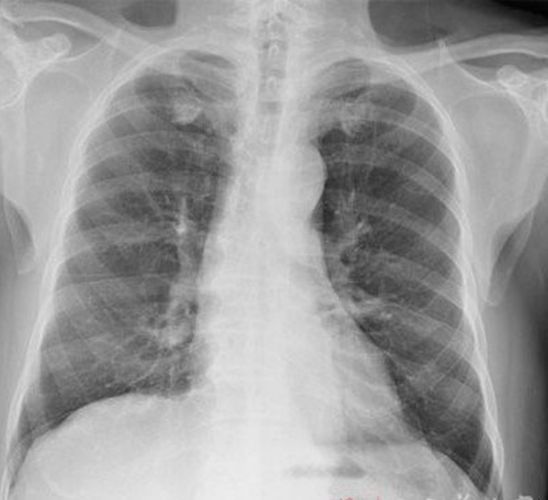

右下肺腺癌 的